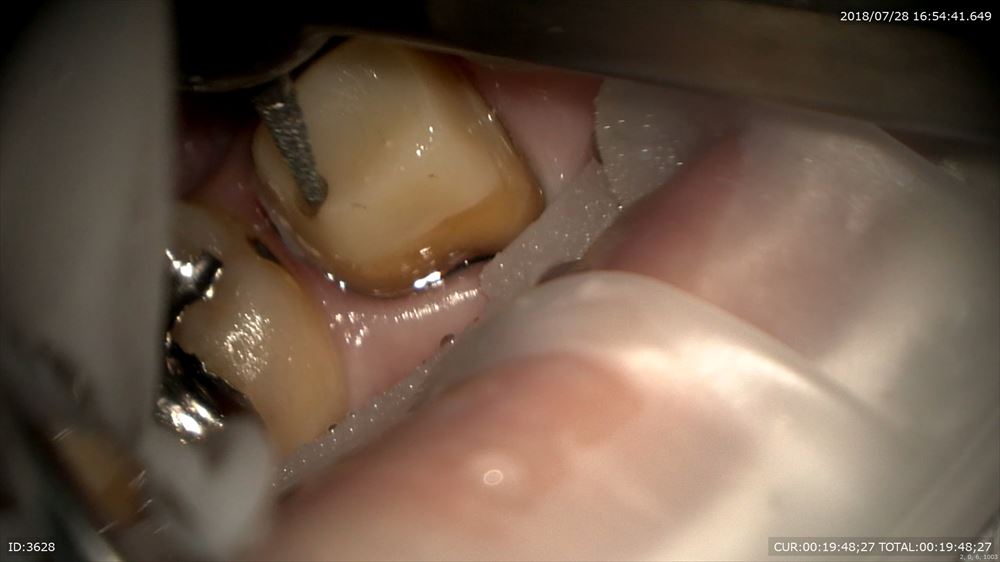

かみ合わせ調整

隙間0の被せ物。

歯がない部分も押してモディファイドオべイド。